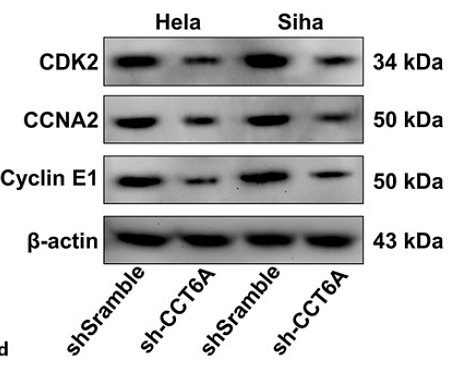

CCT6A regulates cervical cancer cell glycolysis and proliferation under hypoxic conditions via the TCAB1/TERT

Author: Wang Yu, Wang Hongli

PMID: 38657573

期刊: Gynecologic And Obstetric Investigation

应用: WB

反应种属: Mouse,Human

发表时间: 2024 Apr

-